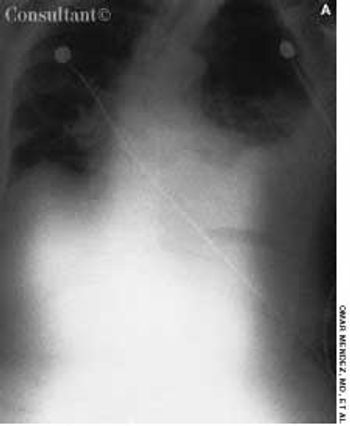

Police brought a delirious, combative 24-year-old man to the emergency department. The patient was unable to provide any history on arrival, but his scarred, blistering lips and his vital signs (blood pressure, 166/102 mm Hg; heart rate, 97 beats per minute; respiratory rate, 24 breaths per minute; and temperature, 38.2°C, or 100.9°F) led to a possible diagnosis of cocaine-induced delirium.